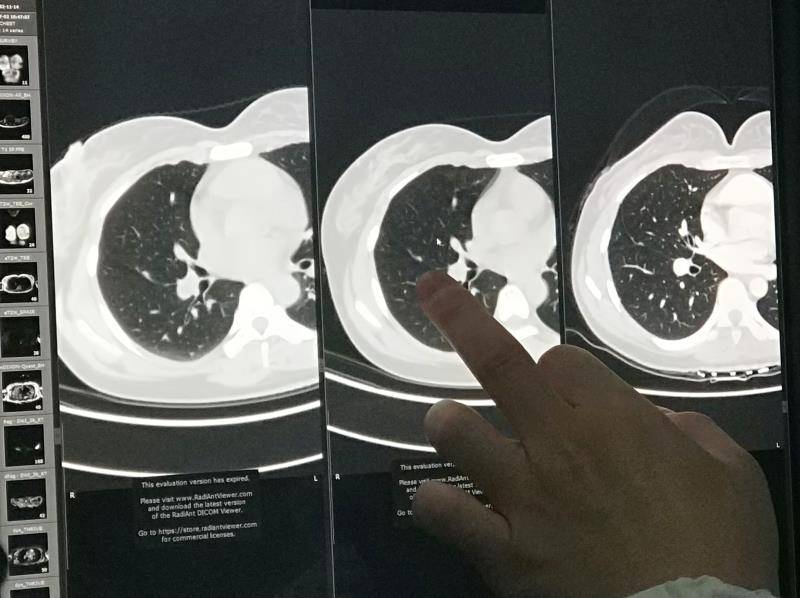

胸膜在CT上是若隐若现的一条线,微小的病灶和肺内结节很容易混在一起。因为一直在胸科随访,我把所有CT的DICOM格式文件拷出来找了太湖边上一位看片子的专家,是的,他一上午只需要看三四个病人,我从来没有在诊室停留过这么长时间,一个小时时间把一年的影像做了详细的对比和解释——胸膜进展!

从确诊开始一直没有被抑制,多发,非常缓慢的进展,只是在胸膜上播散,没有胸腔积液,没有在肺实质内形成小病灶。

韩院长是大咖,在电脑上点了几下就指出来胸膜进展, 大概意思是病灶周边血管生成,放疗没有意义,给出了阿来联合安罗的靶向治疗方案。